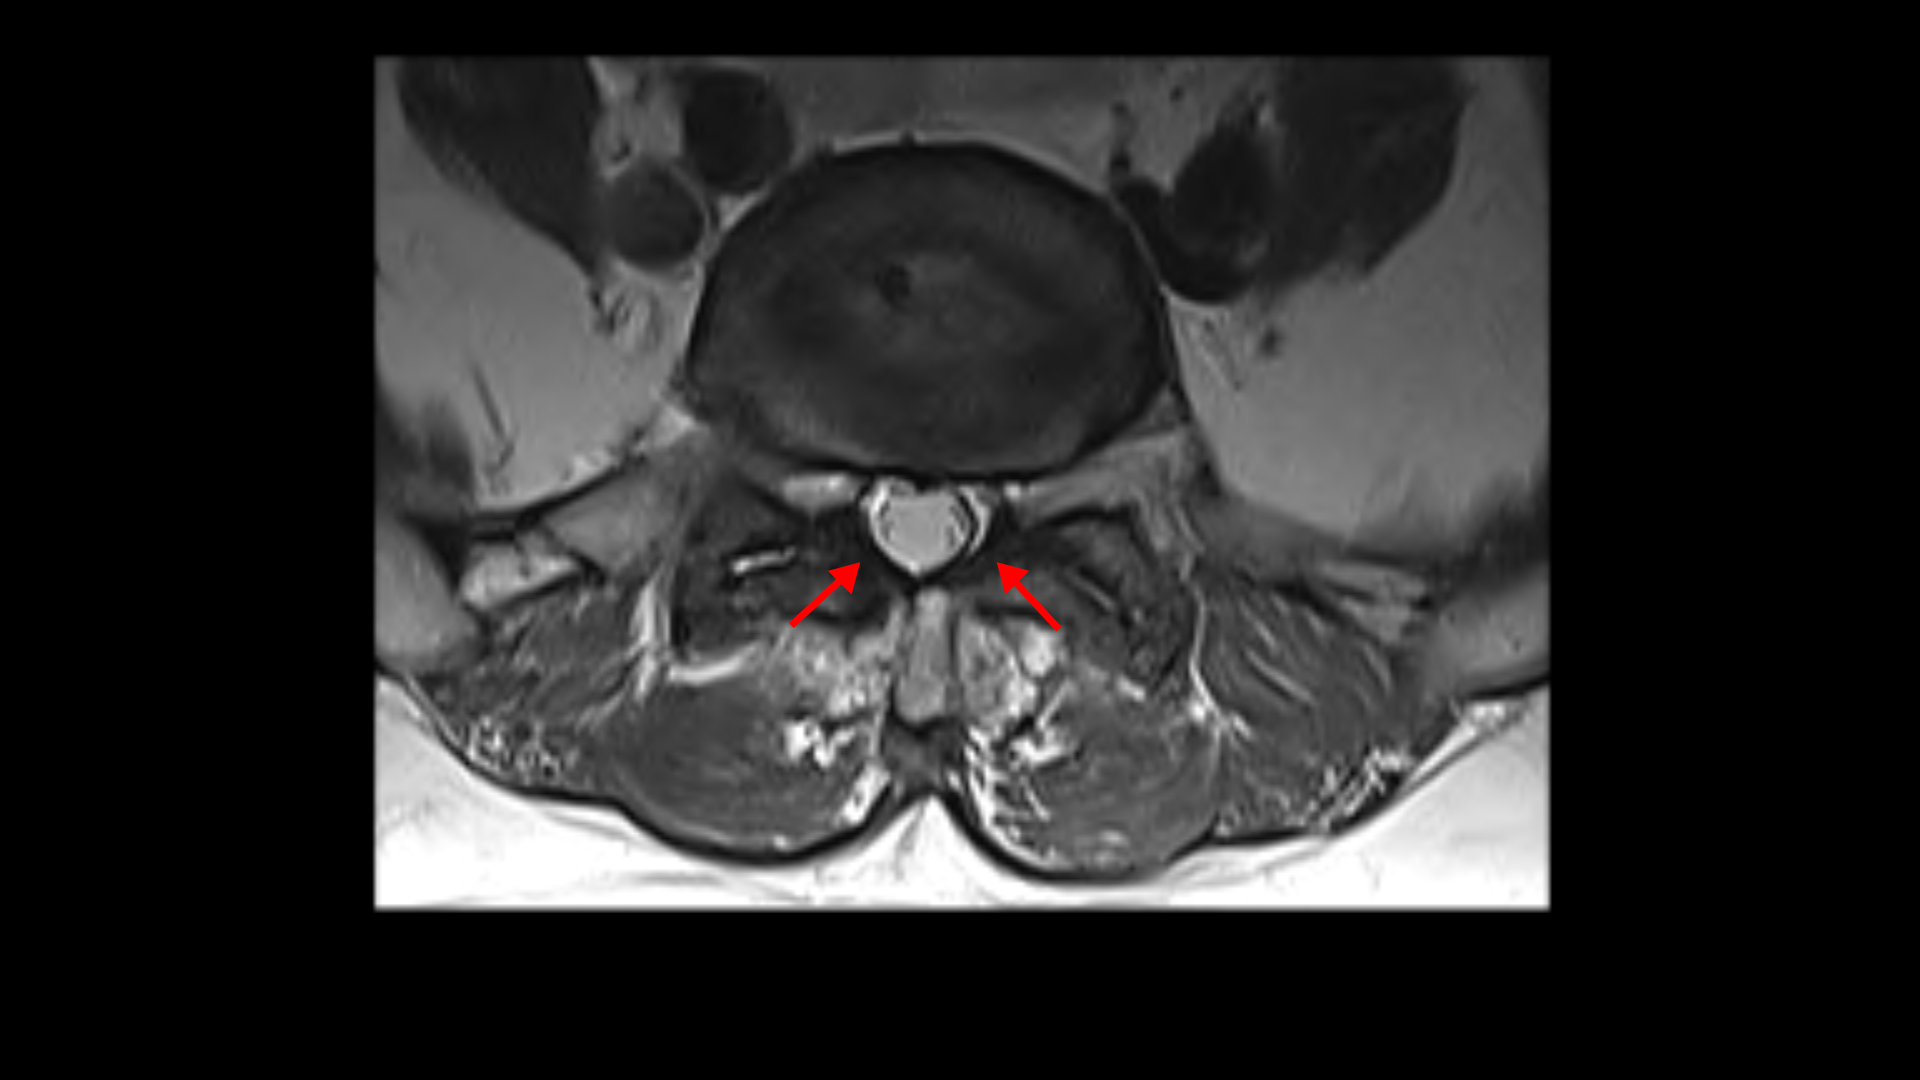

먼저 5번 1번에 척추관 내의 황색인대의 골화 현상이 보이고

후관절의 퇴행도 심해 보입니다.